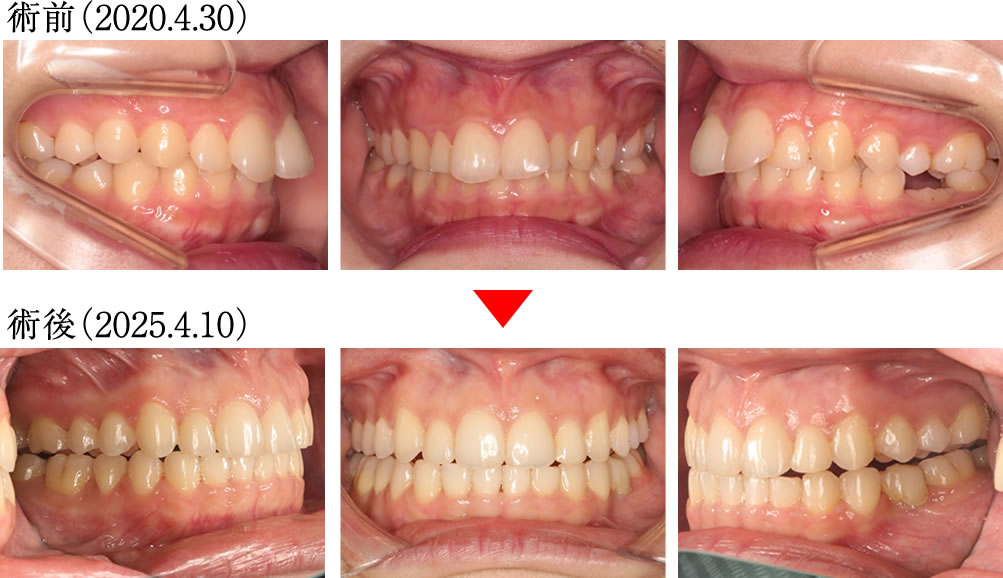

術前では、上顎の前歯が前方に傾斜しながら、深く噛みこんだ歯並びでしたが、術後は上下の歯が理想的な傾斜と被蓋関係で噛んだ歯並びになりました。

術前では、歯列全体が狭く、不均衡に乱れたアーチの歯並びでしたが、術後は理想的に並んだキレイで大きなアーチになりました。